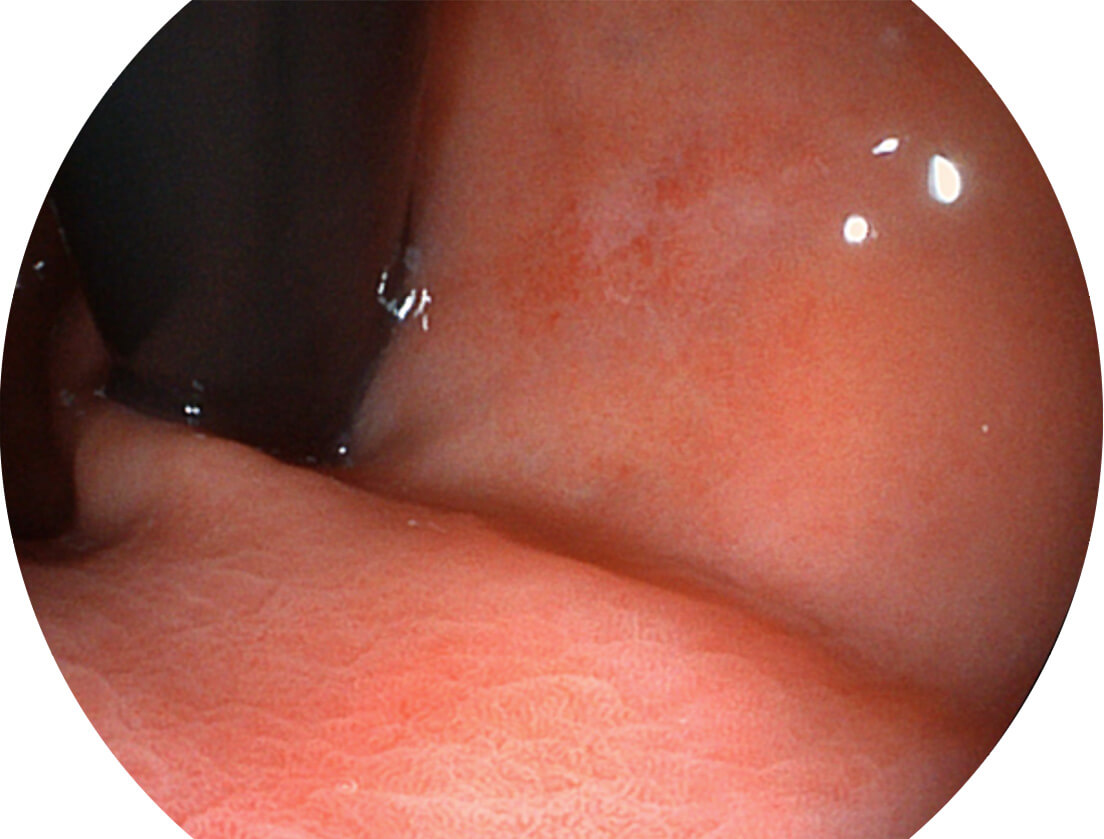

Versatile Intelligent Staining Technology, VIST

强调浅层黏膜结构的同时,保证照明亮度和提升浅层微血管与中层血管颜色对比度,病变边界更清晰。

白光图像

VIST图像